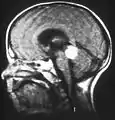

Aspect of trilateral retinoblastoma on MRI

Inherited forms of retinoblastomas are more likely to be bilateral. In addition, inherited uni- or bilateral retinoblastomas may be associated with pineoblastoma and other malignant midline supratentorial primitive neuroectodermal tumors (PNETs) with a dismal outcome; retinoblastoma concurrent with a PNET is known as trilateral retinoblastoma.[8] A recent meta-analysis has shown that survival of trilateral retinoblastoma has increased substantially over the last decades.[9]

In about two-thirds of cases,[18] only one eye is affected (unilateral retinoblastoma); in the other third, tumors develop in both eyes (bilateral retinoblastoma). The number and size of tumors on each eye may vary. In certain cases, the pineal gland or the suprasellar or parasellar region (or in very rare cases other midline intracranial locations) is also affected (trilateral retinoblastoma). The position, size, and quantity of tumors are considered when choosing the type of treatment for the disease.

Traditional ultrasound B scan can detect calcifications in the tumour while high-frequency ultrasound B scan is able to provide higher resolution than the traditional ultrasound and determine the proximity of the tumour with front portion of the eye. MRI scan can detect high-risk features such as optic nerve invasion; choroidal invasion, scleral invasion, and intracranial invasion. CT scan is generally avoided because radiation can stimulate the formation of more eye tumours in those with RB1 genetic mutation.[26]